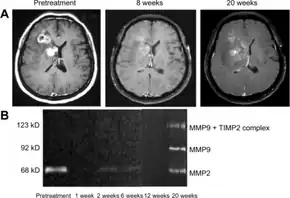

Brain cancers

Bevacizumab slows tumor growth but does not affect overall survival in people with glioblastoma multiforme.[25] The FDA granted accelerated approval for the treatment of recurrent glioblastoma multiforme in May 2009.[26][27] A 2018 Cochrane review deemed there to not be good evidence for its use in recurrences either.[25]